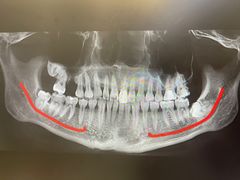

• 牙博士口腔品牌连锁(杨浦店)

• -牙博士口腔品牌连锁(杨浦店)